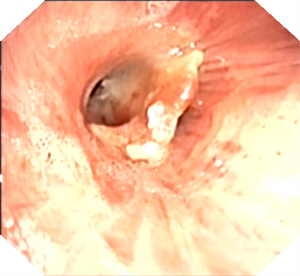

一位外地老年男性患者,因 “肺炎” 一直咳嗽、气喘不愈,活动量差。在当地医院多次住院治疗,症状仍无明显改善。后因 “液气胸” 急诊入我院,呼吸科医生仔细阅片后发现,患者右中间段支气管内有一类圆形 “新生物” 阻塞管腔。收住院后,呼吸内镜团队为患者进行全麻支气管检查,清晰见到右中间段支气管内一黄豆异物阻塞。由于异物 “圆滑”,直接取出困难,医生巧妙地用圈套器 “捆扎” 住黄豆,顺利完整拉出,患者快速康复出院。